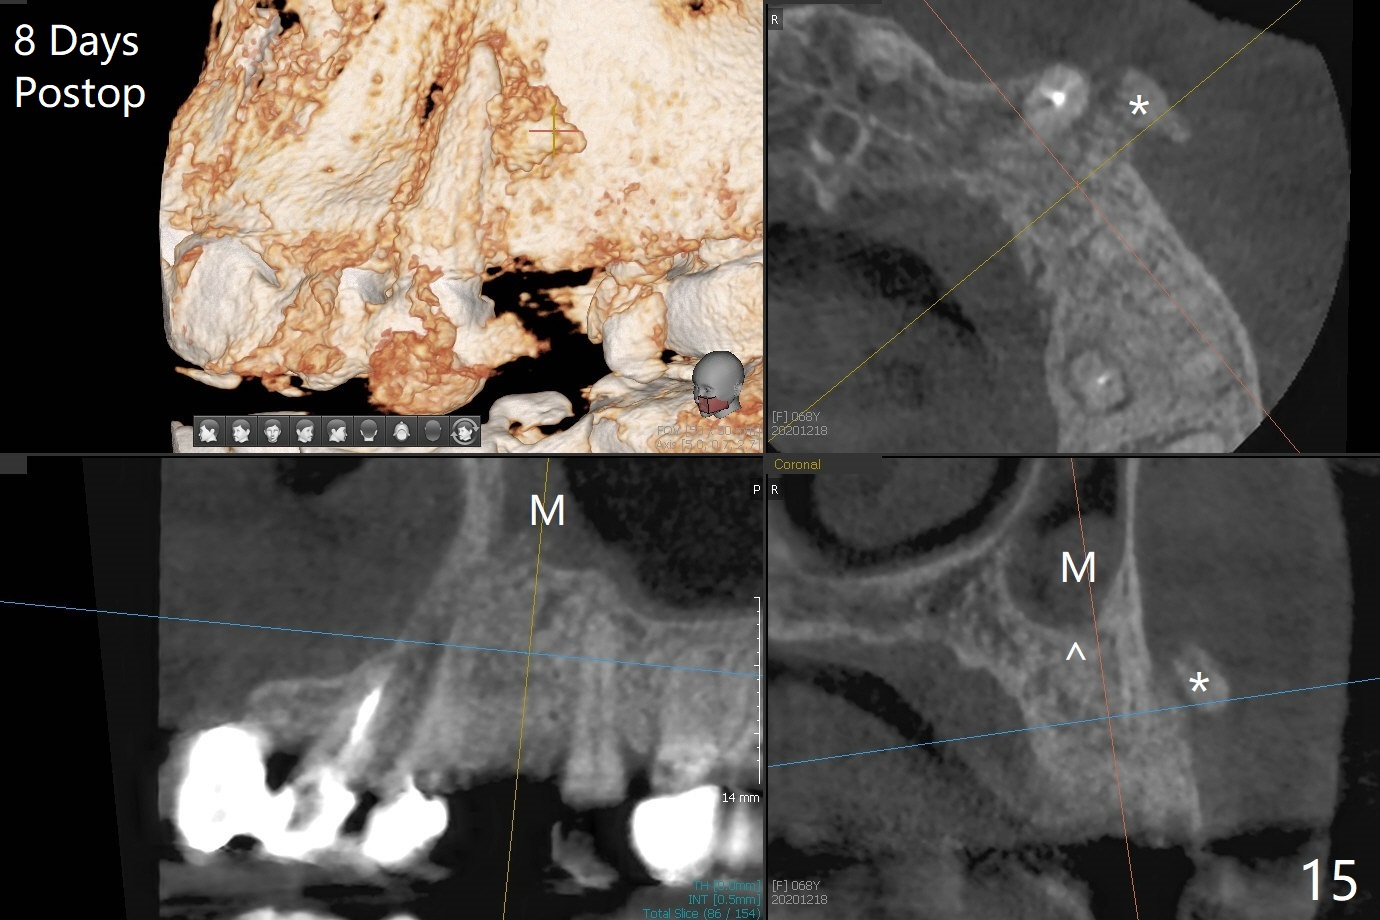

68岁女左上4颊侧瘘道(图一:*),与根尖颊侧骨板缺失相通,其实腭侧根尖周围病变更大(也与颊侧窝相通),术中没有注意腭侧根接近3(图二:P),稀里糊涂的基本顺着腭侧根(颊侧)走向钻洞(图四,与图三理想方向对比),突然记起术前设计钻洞必须在腭侧牙槽窝远中颊侧,在远中建立新洞眼(图五),之后无法再次建立新洞眼,只好利用同一个侧面切割钻头将钻洞往远中移位,同样效果不佳(图六),最后只好放弃,放置粘性骨粉(图七:*),覆盖PRF膜,6个月胶原膜,PGA缝线,牙周胶水。术后重新分析表明顺着腭侧牙槽窝种植与尖牙还是有分离(图八,九:*),因为牙槽窝是斜型的(图十:黑色),不过离颊侧骨板也接近(图八:B)。所以钻洞必须斜型针对远中骨壁,表浅些(图十一:红色箭头);一旦进入骨板,改变角度(图十二:红色箭头),适当矫枉过正,随着植体增大,钻洞会往近中偏移(白色箭头)。最好植体方向理想(图十三)。不过植骨后钻洞偏移可能性比较少。缝线和牙周胶水似乎是一个稳妥固定胶原膜方法。术后病人抱怨水肿严重,术后八天颊侧根尖隆起是由于骨粉推出骨板之外(图十五,十六:*),上颌窦底板无意穿孔(^)伴有上颌窦膜(M)增厚,与术前对比(图十七:上颌窦窦腔清晰)。术后一个月6个月吸收膜不见了,大多数缝线已经脱落,最后两根缝线撤除后,牙槽窝开口已经关闭,好像主要成分是骨粉(图十八)。术后5个月牙槽嵴宽,角化龈也宽,好像可以植入4x11.5毫米植体(图十九)。